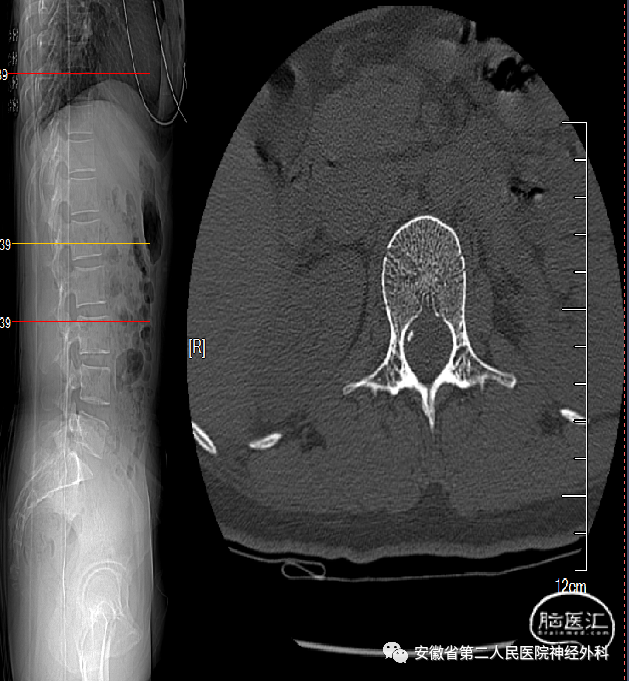

术前CT